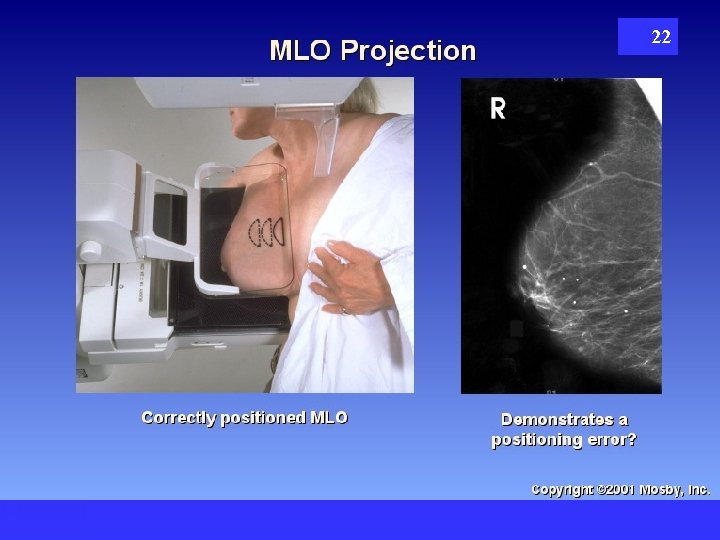

22